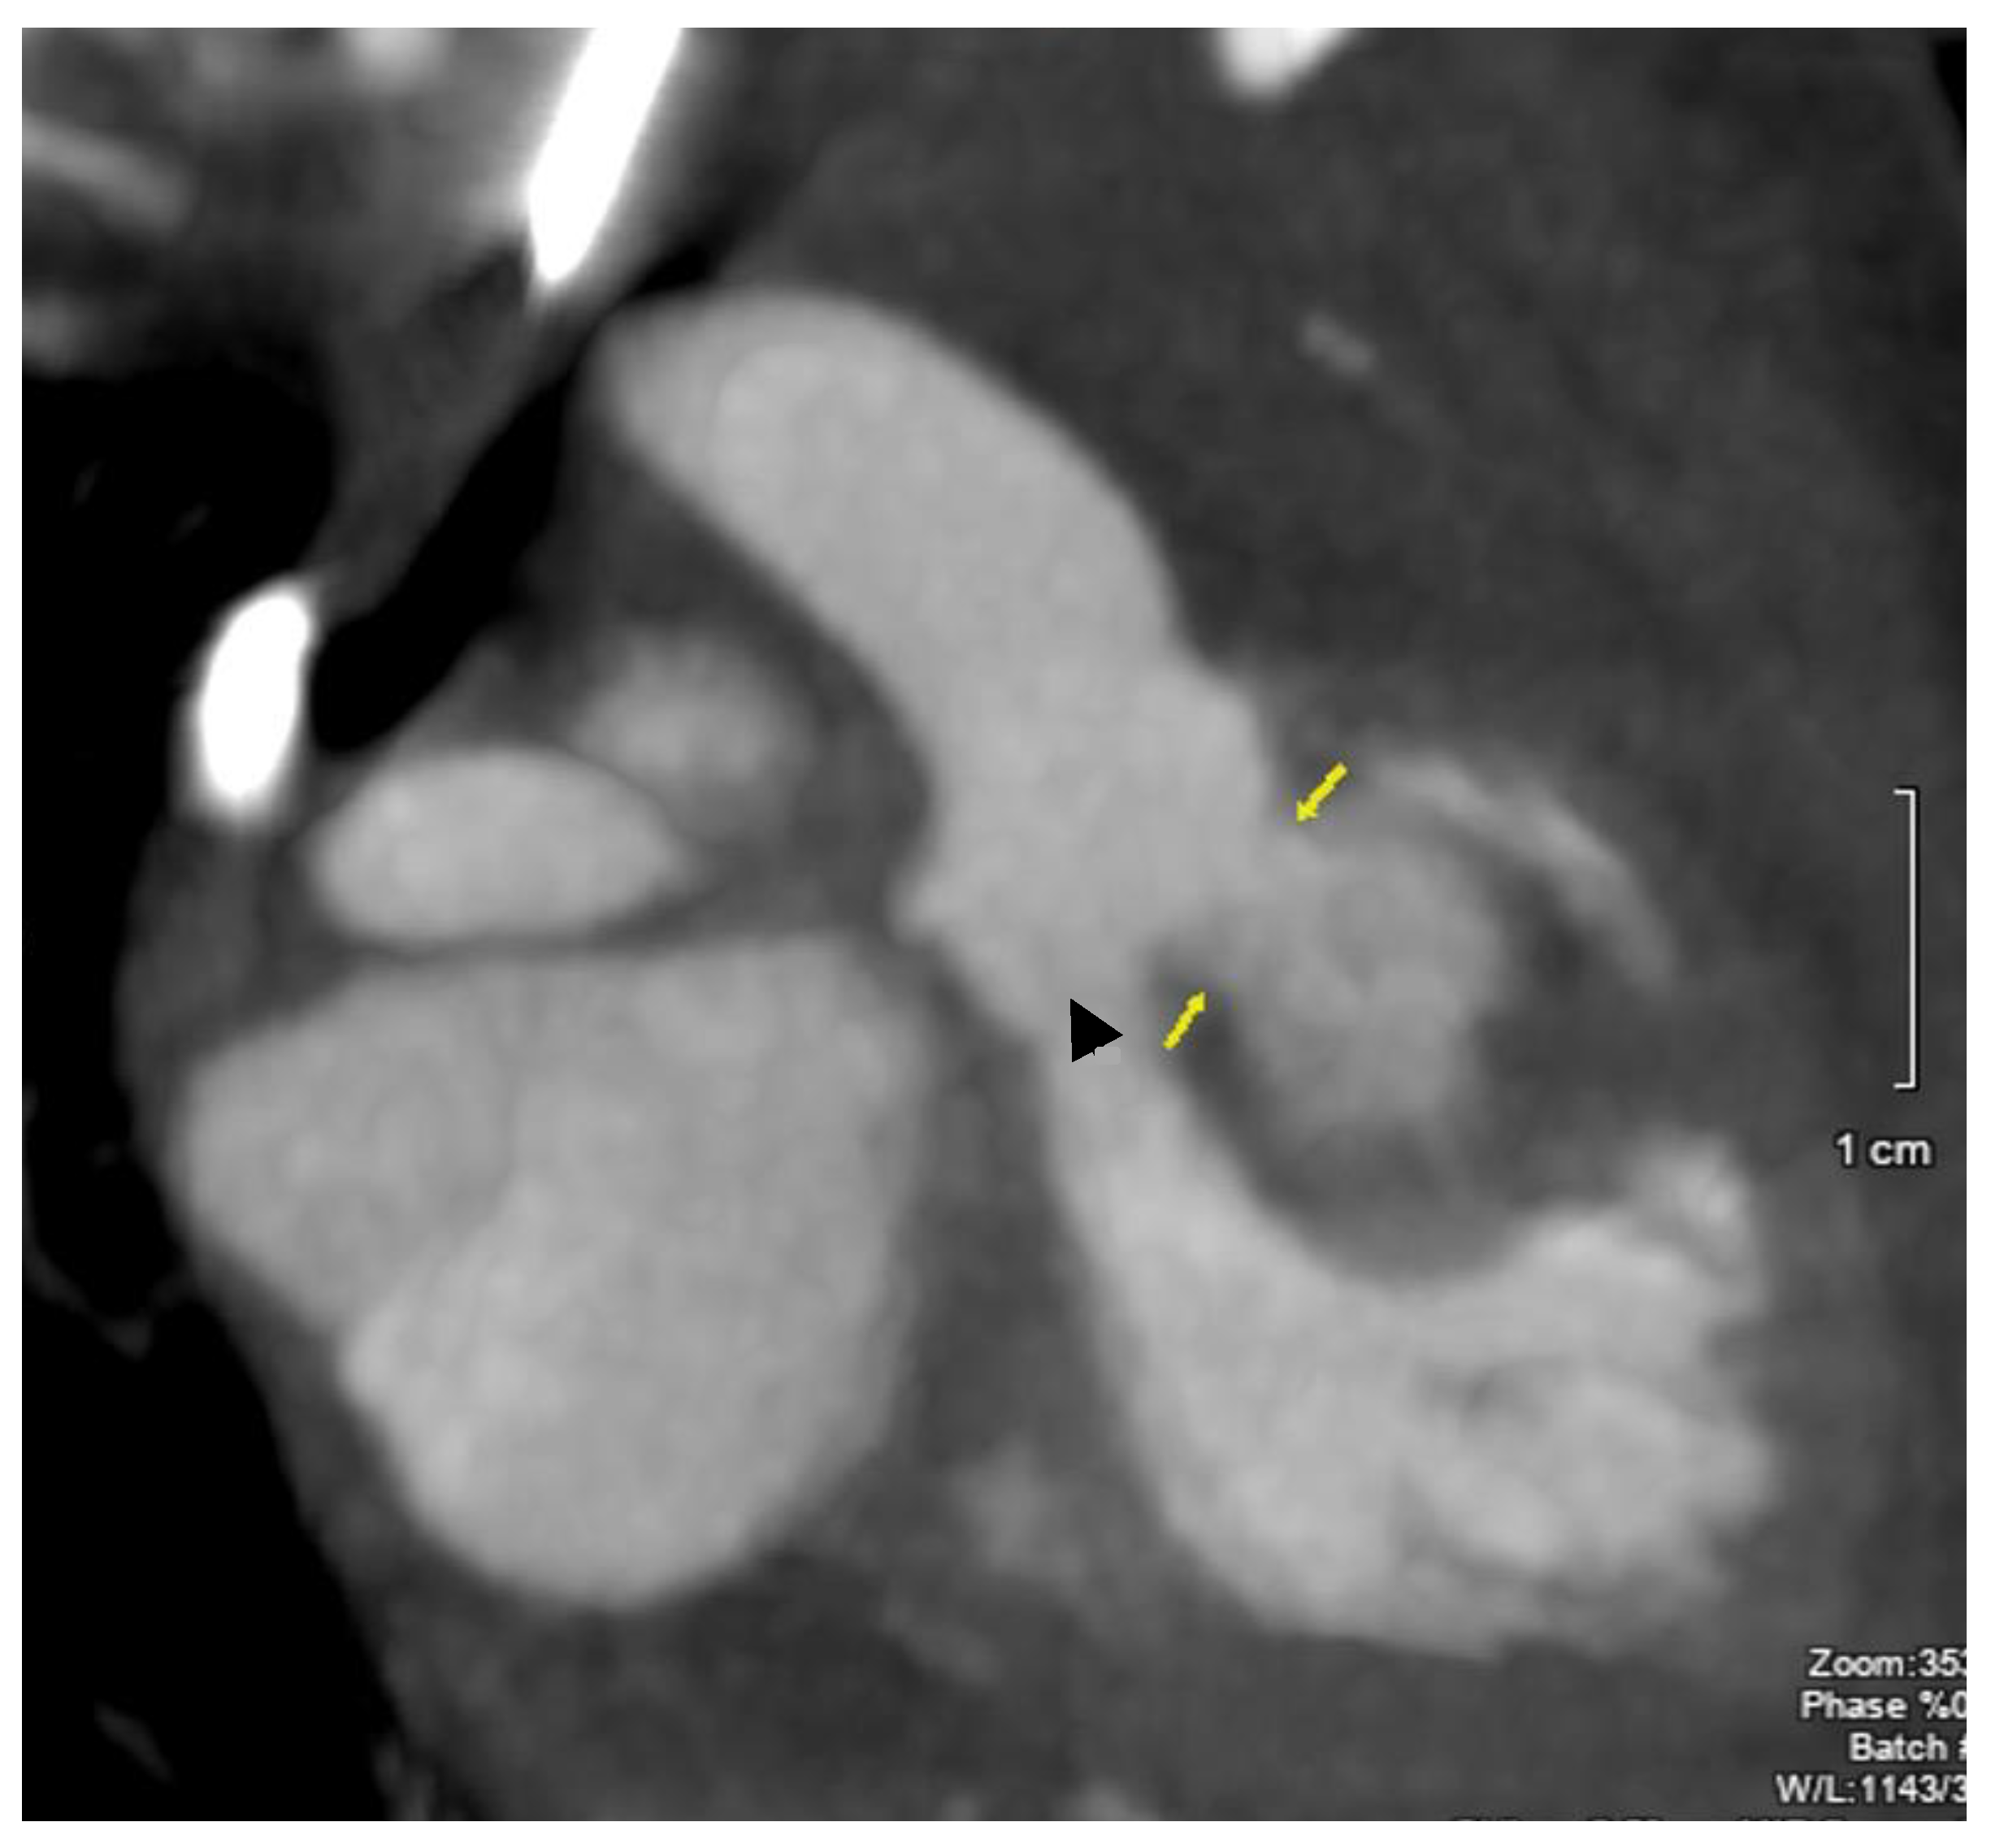

2. Case Description